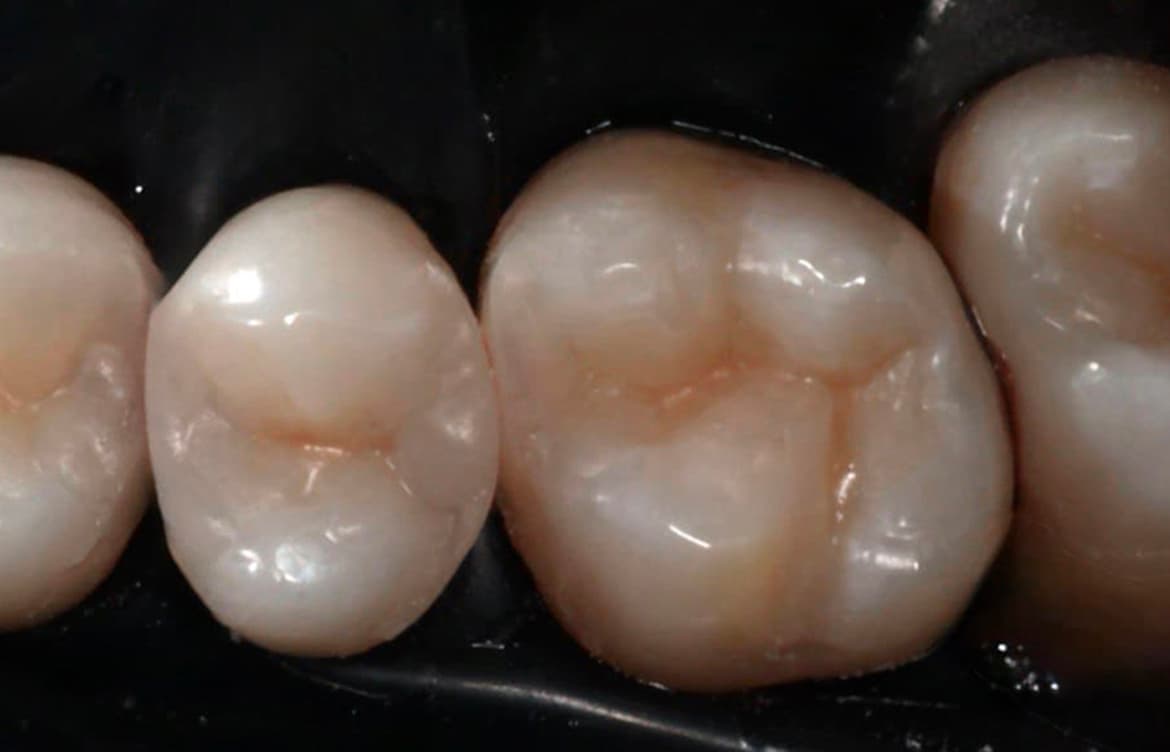

Наши работы